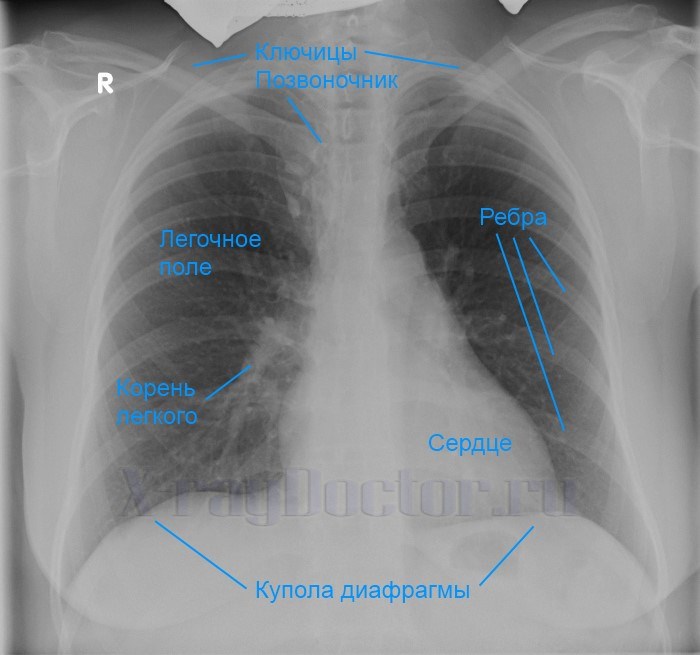

Снимок грудной клетки здорового ребенка: примеры и диагностика